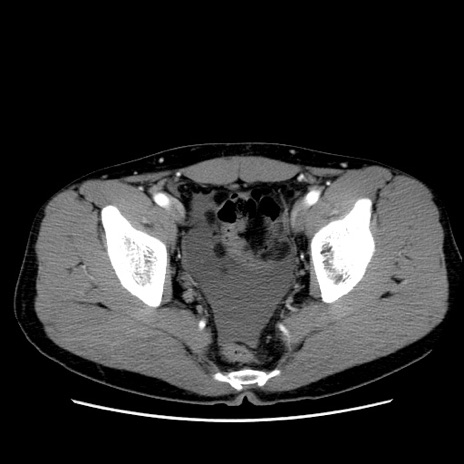

症例36(横断像)

【症例】20歳代 男性

【主訴】心窩部痛

【現病歴】今朝より上腹部痛あり。一旦軽快していたが再度出現したため救急要請。昨日夕に白身の魚を含む刺身を食べた。

【身体所見】BP 136/89mmHg、HR 74/min、BT 37.0℃、腹部:膨満、軟、心窩部に圧痛あり。反跳痛なし、筋性防御なし、腸雑音やや亢進あり。

【データ】WBC 17700、CRP 0.48